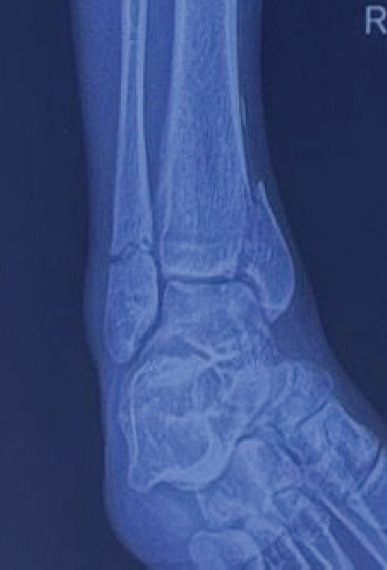

Case report: A 34-year-old male presented with multiple fractures, including a triple-segmental shaft femur fracture, following a high-energy road traffic accident. An intramedullary nail was used for closed reduction and internal fixation of the femur fracture, which provided stable fixation while preserving the blood supply and minimising soft-tissue damage.